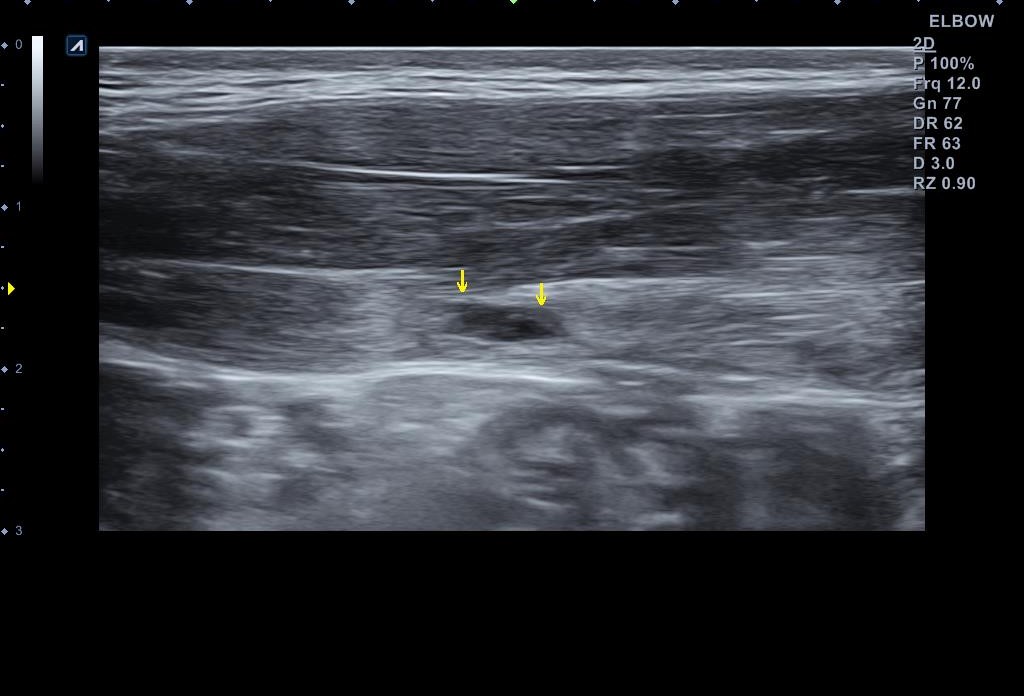

x-ray 검사와 초음파 검사를 진행했습니다. x-ray 검사는 특별한 소견이 없었구요, 초음파 검사는...

복직근 파열부위(노란 화살표) vs 정상부위

복직근 파열부위

나 : 복직근 파열이 맞네요.

나 : 근육이 많이 찢어진건 아닌데... 우선 일주일 간격으로 초음파 검사를 통해 호전여부를 확인하고 운동 복귀 시기를 결정하셔야 합니다. 그때 까지는 스매싱같은 동작은 하시면 안됩니다.